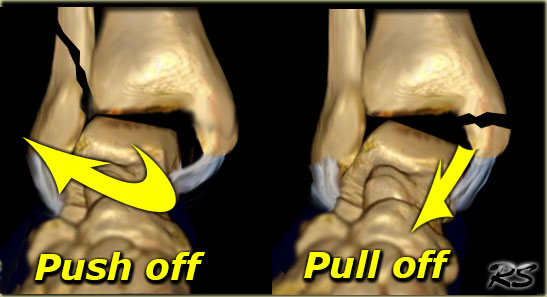

Pull-off or Push-off fractures

The shape of a fracture indicates which forces were involved. An oblique or vertically oriented fracture indicates 'push-off'.

A transverse or horizontal fracture is the result of a 'pull-off' or avulsion.

On the left image the lateral malleolus is pushed off by exorotation of the talus.

On the right image the medial malleolus is pulled off by the medial collateral ligament due to pronation of the foot.